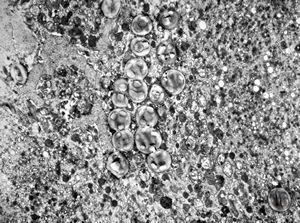

F, 24y. | molluscum contagiosum … virions

F, 24y. | molluscum contagiosum

F, 24y. | molluscum contagiosum